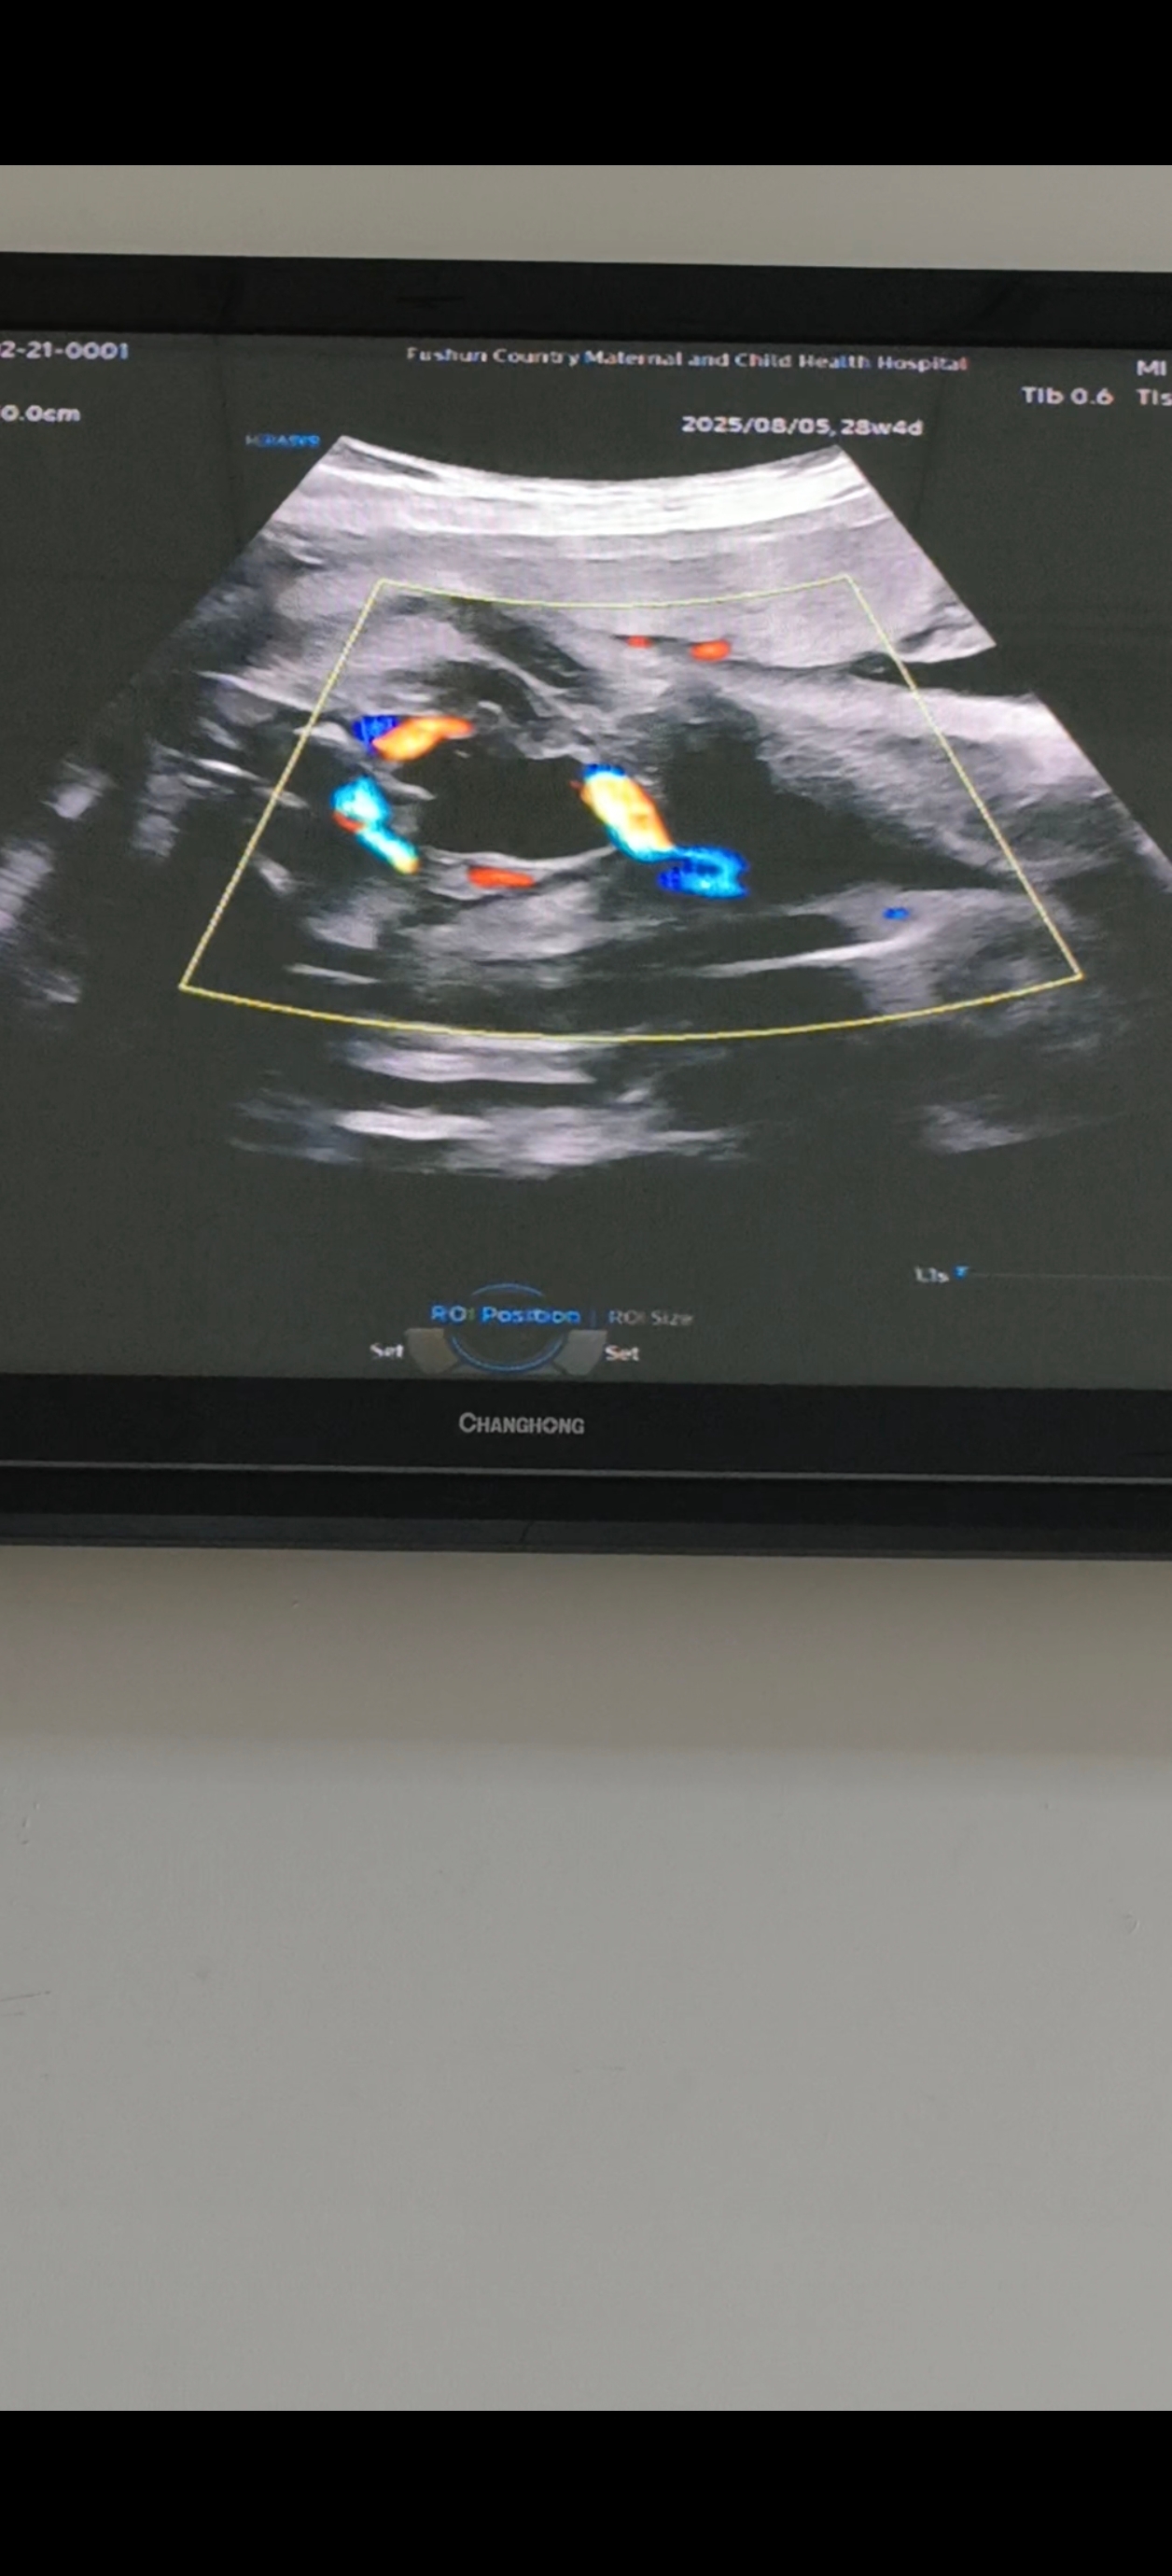

(31周和36周的彩超,孩子貌似没怎么长,除了胎位变了,别的变化都不大)

听了之后我也提心吊胆的,本来嘛,孩子在肚子里没生出来怎样都不放心,还是第一胎。昨天晚上担心的都睡不着,老公说不放心的话让我早上起来就去做个检查。今天去医院,大夫摸胎位说,头在下面,胎心正常,我还不敢相信,问她真的吗?她又摸了一遍说她摸的是这样,但是毕竟隔着肚皮,一切以彩超为准。我又做了个彩超,终于确定就是在下面了。就是我家宝儿个子太小了,大小值是标准范围里的最小值,并且还不到五斤,老公说都怪我,肉也不喜欢吃,鸡蛋也不吃,不过我的体型也不是生胖娃的料。我决定剩下这一个月,一定要努力补回来点。